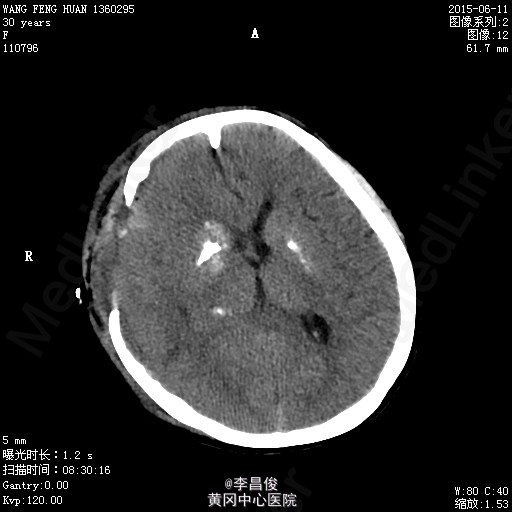

入院完善相关检查:血常规:血红蛋白 105.1g/L,血小板 95*10^9/L,尿常规:蛋白 -,肝功能:谷丙转氨酶 77.9U/L,尿酸 426.7umol/L,凝血机制:D-二聚体 2267ng/ml。 血脂:甘油三酯:3.31;低密度脂蛋白:5.46,甲功、心肌三项、心脏彩超正常, 给予对症处理,患者于6月4 日8:42分在会阴左侧切下以LOA位顺利娩出一活女婴,产程顺利,产时血压最高达160/110mmHg,给予心痛定一粒舌下含服,产后回病房后监测血压在100-140/70-90mmHg之间波动。6月7日5点多头痛明显,急查头部CT提示:右侧额颞顶部硬模下血肿。请神经外科急会诊,建议转专科治疗。转外科后,患者意识障碍加重,6月8日17:30时急诊全麻下行“右侧开颅硬膜下血肿清除+去骨瓣减压术”,术后转重症医学科。稳定后拔除气管插管后转回专科,行抗感染、止血、神经营养、脱水治疗,定期换药及CT复查,后出现癫痫发作,给予抗癫痫治疗。6月13日患者癫痫发作后呈持续状态,药物控制不理想,故转入ICU进一步监护治疗。患者神志昏迷,给予持续泵入丙戊酸钠、咪达唑仑控制抽搐,适当脱水、抗感染、营养支持及对症处理,并及时复查相关检查。患者癫痫控制后于17/6日顺利拔除气管导管。于17/6日再次癫痫发作1次,很快缓解。转神经科继续治疗:患者神志清楚,精神、食欲一般,诉左侧肢体无力伴麻木,无抽搐发作,右侧肢体肌力尚可,左侧肢体肌力3级。肌张力不高。继续给予抗癫痫、适当抗感染、肢体康复训练及对症支持治疗,一周后行颅脑MRI:未见明显异常;查体:心肺听诊(-),腹软,压痛反跳痛,双下肢无水肿,右侧肢体肌力尚可,左侧肢体肌力5级-,病理征(-),给予办理出院。

患者产前产后血压基本维持在正常水平,尿蛋白阴性,癫痫可能与额颞部出血相关性大,双侧基底节区对称行钙化有可能是Fahr综合征,为遗传性疾病,家族是否有类似病例?